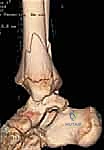

- الأشعة المقطعية ثلاثية الأبعاد (3D CT Scan): تُعد ضرورة حتمية في حالات كسور تيلوكس والكسور ثلاثية المستويات، أو أي كسر يمتد داخل المفصل. توفر الأشعة المقطعية خريطة دقيقة لحجم القطع العظمية ومقدار التباعد (Displacement)، مما يساعد في التخطيط الجراحي المسبق.